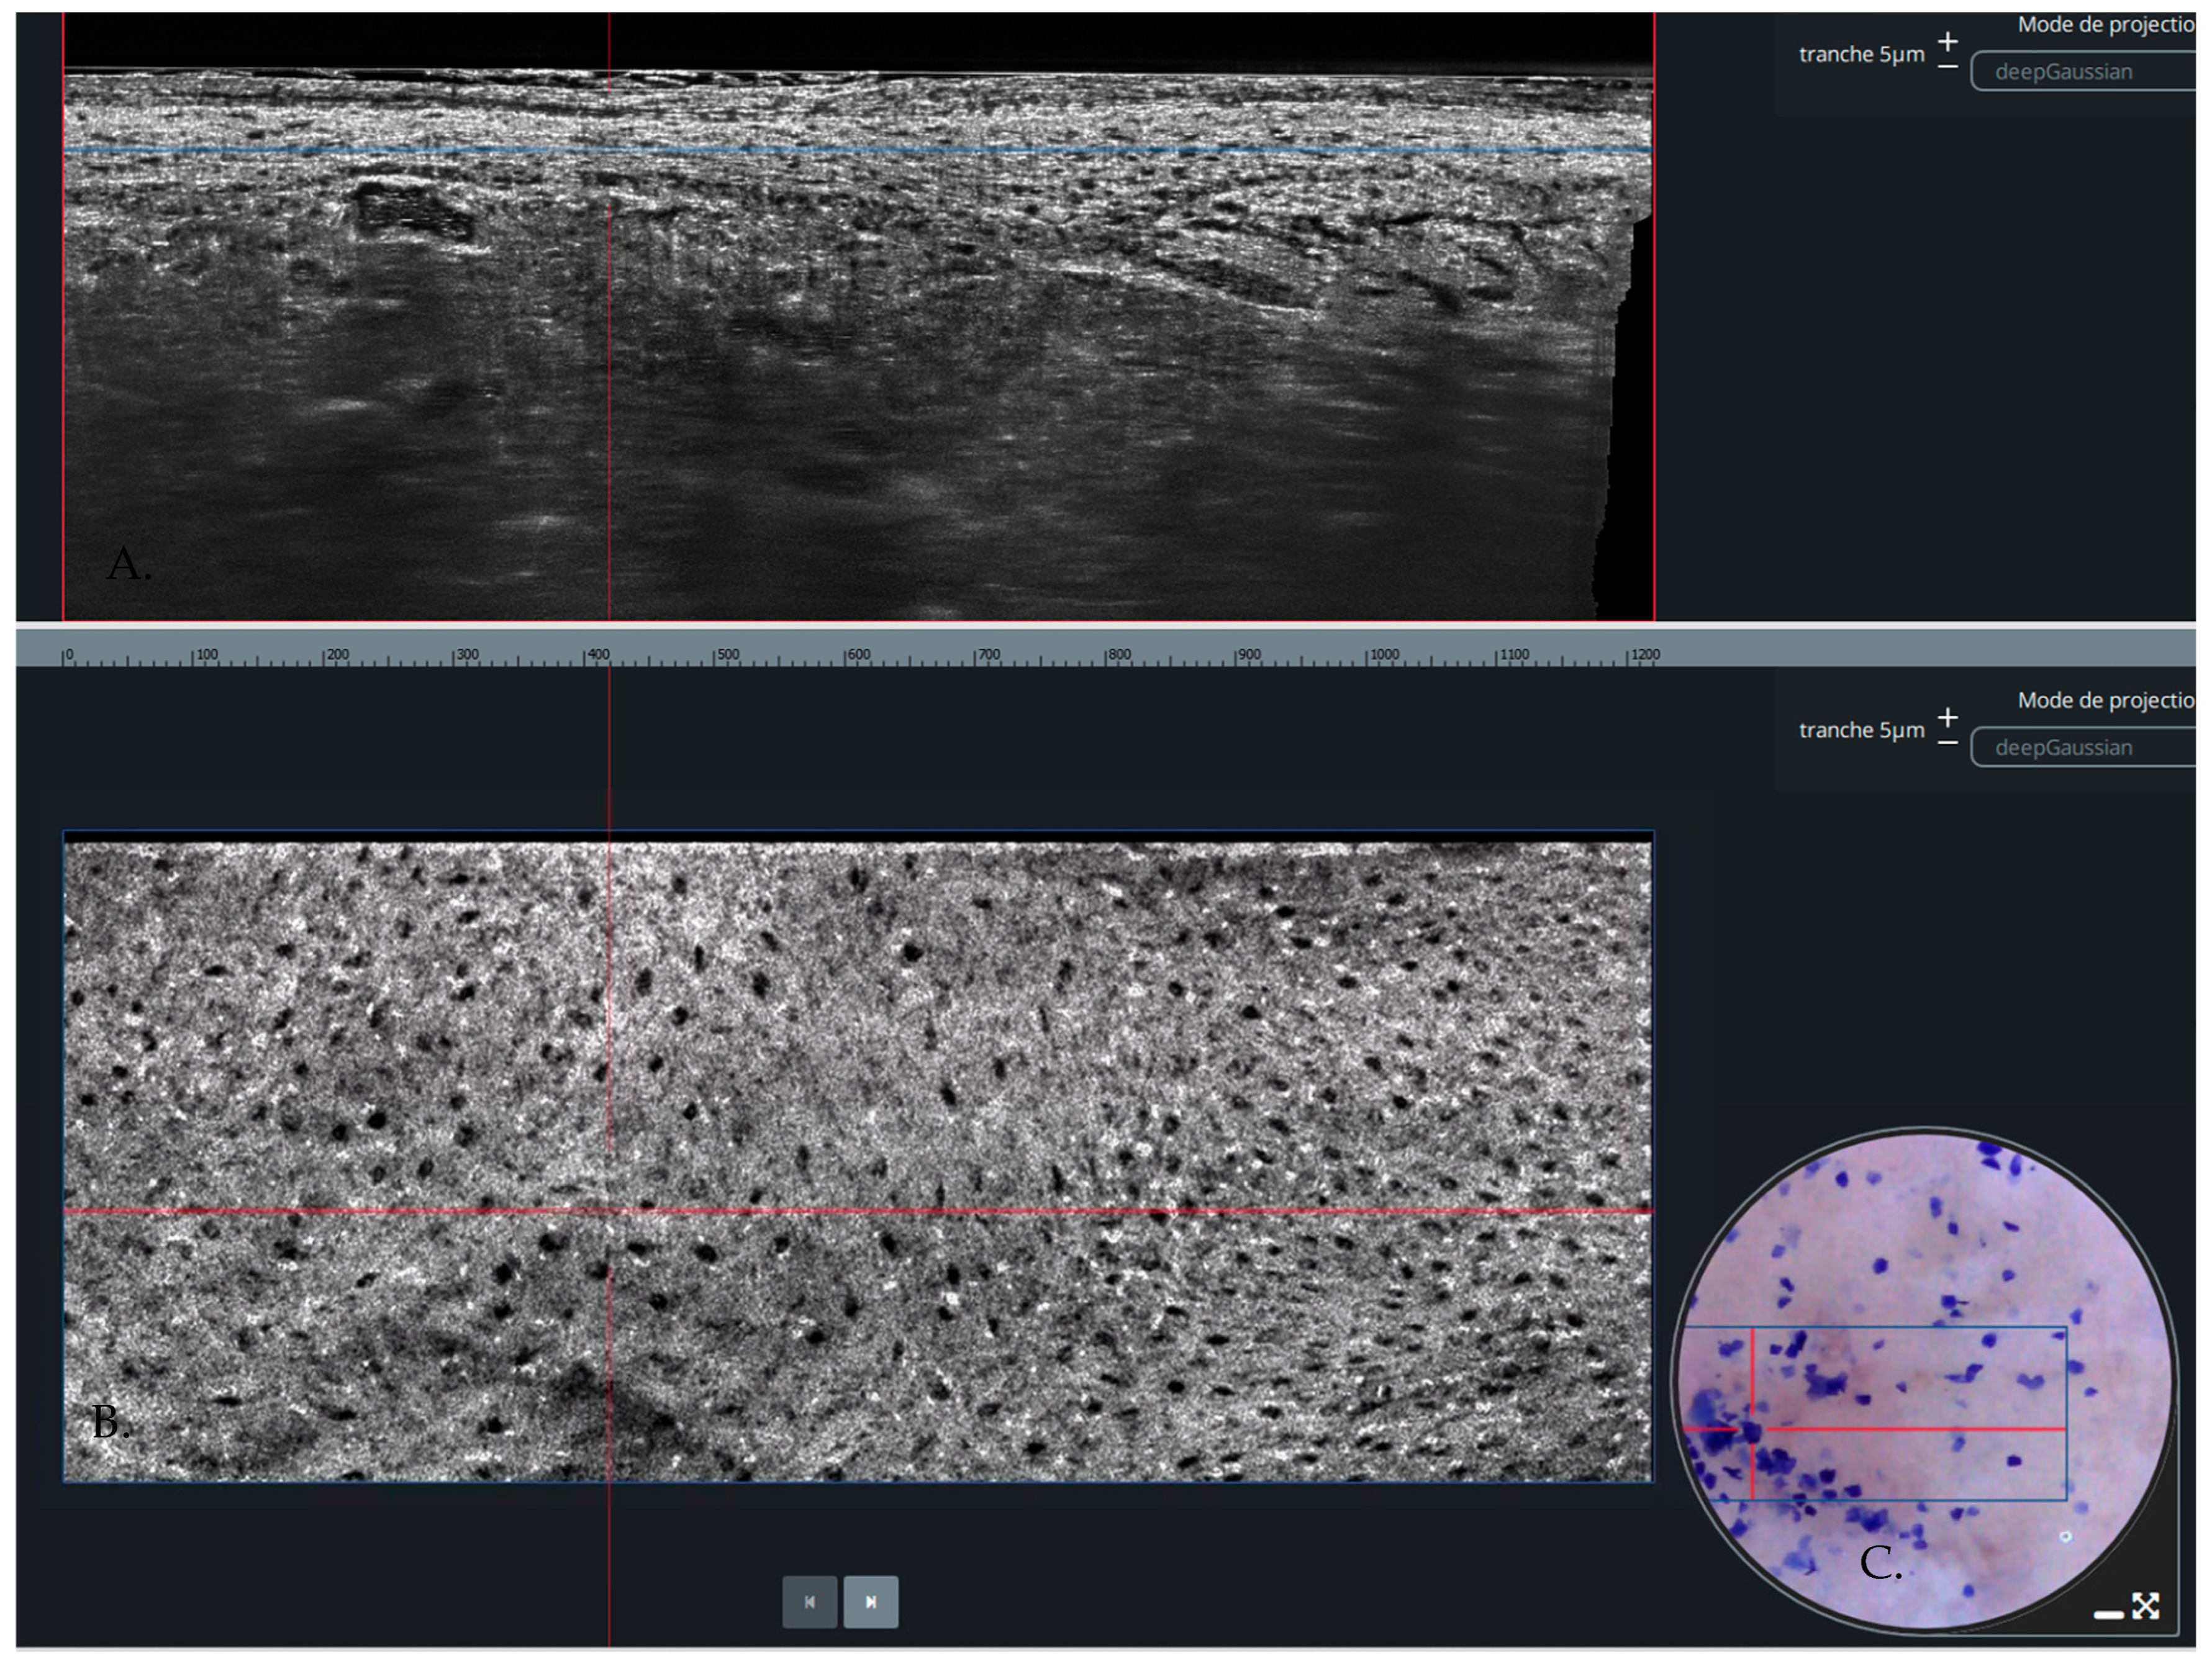

1. Introduction

3. Results

3.1. Description of Studies Included

3.3. Per-Lesion Analysis